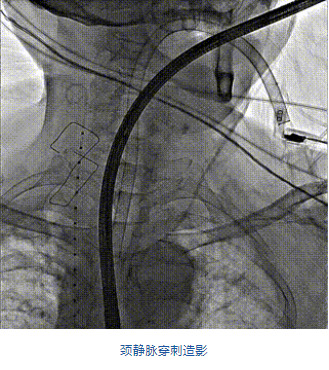

團隊前期經(jīng)過多次討論,制定了周密的手術(shù)策略和預(yù)案。由于患者已是近九旬的超高齡老人,傳統(tǒng)外科開胸手術(shù)風(fēng)險極高,純介入經(jīng)血管三尖瓣替換能夠明顯減少創(chuàng)傷。術(shù)中陳茂及馮沅教授結(jié)合體表定位在造影指示下精準穿刺右側(cè)頸靜脈并預(yù)置兩把血管縫合器。成功建立經(jīng)皮血管入路后在食道超聲和DSA的引導(dǎo)下順利完成人工瓣膜植入,術(shù)后超聲和造影顯示人工三尖瓣同軸性良好,瓣架固定牢靠,無反流和瓣周漏,平均跨瓣壓差降為1mmHg。術(shù)畢收緊預(yù)置的血管縫合器縫線完成止血,縫合效果滿意,在手術(shù)室即刻拔除氣管插管。